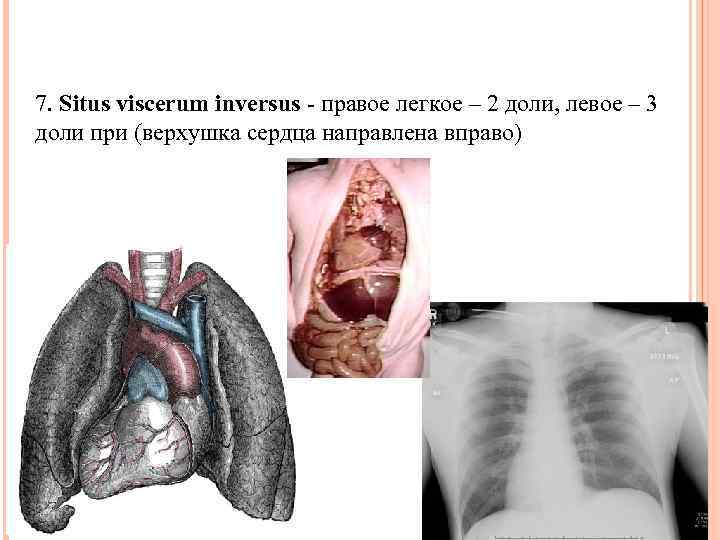

7. Situs viscerum inversus - правое легкое – 2 доли, левое – 3 доли при (верхушка сердца направлена вправо)

7. Situs viscerum inversus - правое легкое – 2 доли, левое – 3 доли при (верхушка сердца направлена вправо)